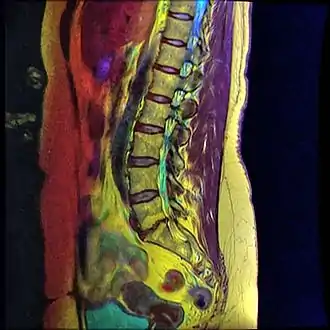

| Grade 1 retrolistheses of C3 on C4 and C4 on C5 | |